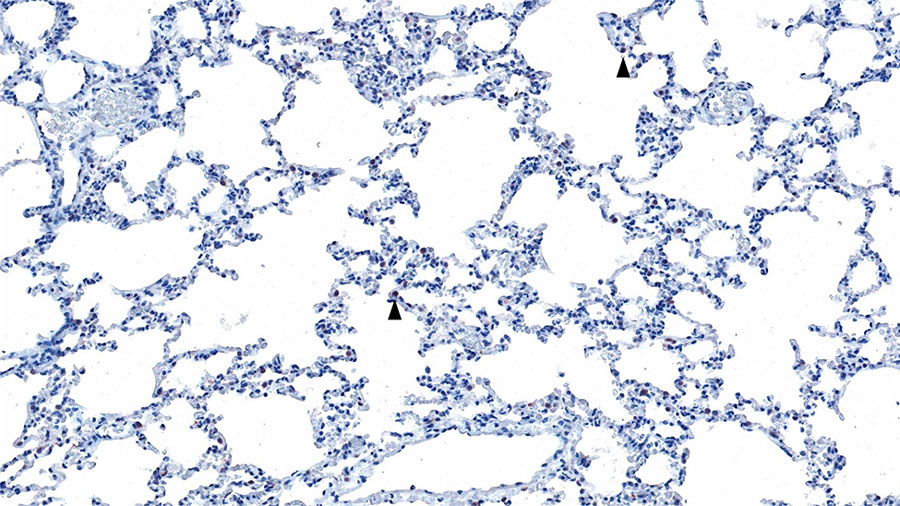

Figure 3. Histopathology of lung from a naturally infected flying fox from a study of natural Hendra virus infections in captive Australian black flying foxes, Queensland, Australia. Immunohistochemistry of bat 4, left caudal lung lobe for Hendra virus (nucleocapsid protein) using a cross-reactive Nipah virus nucleocapsid polyclonal antisera showing scattered interstitial mononuclear cells with finely granular cytoplasmic immunolabelling (arrowhead). Original magnification ×200.